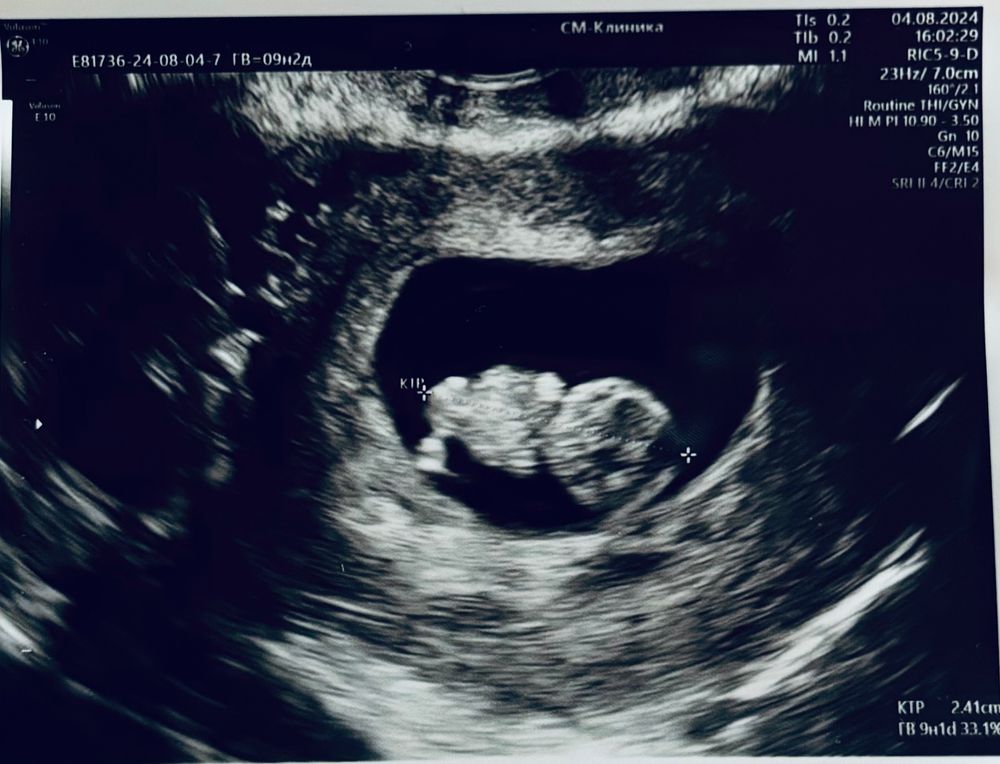

УЗИ, 9н2д ✨

Результаты УЗИСходила на узи, впервые увидела как малыш двигает ножками и ручками 🥹 волшебство да и только!

КТР 24мм, по сроку всё хорошо, никаких нареканий нет.

Алёна, ха! так если круг - голова, овал - тело, четыре тырёчка - ноги и руки 😂 конечно, пока не детально так, но всё ходуном ходило, танцы прям 😂 очень мило! Благодарю Вас, взаимно! Легких родов в срок 🌷🥰